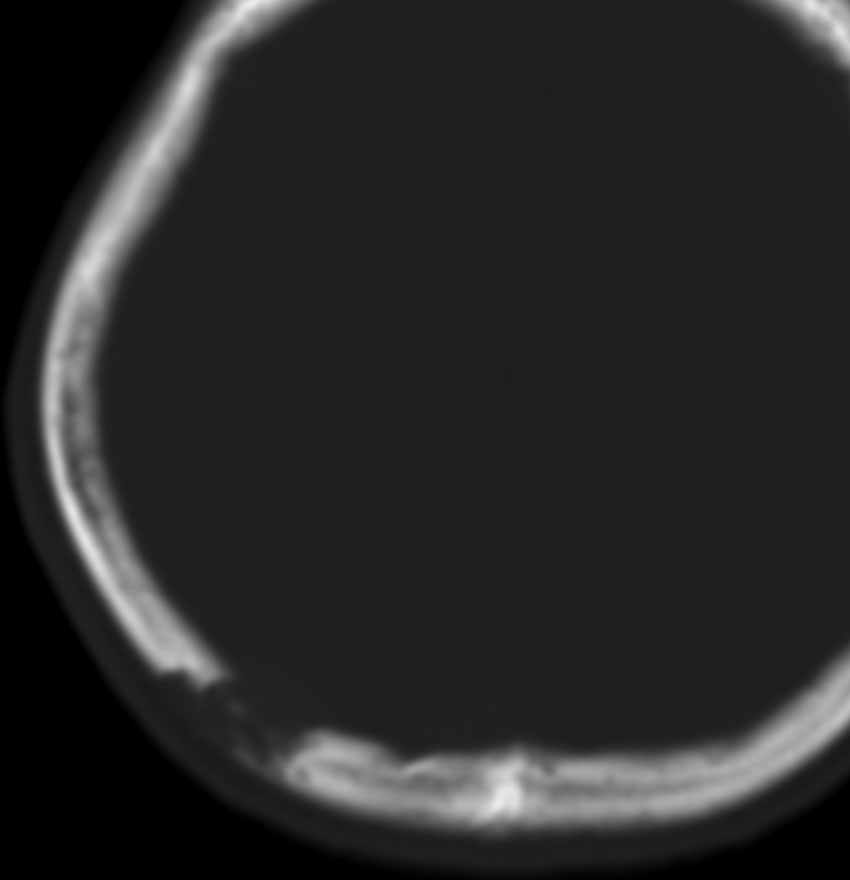

生検術だけして経過を見ると骨欠損が修復される

中年の女性の頭頂部に発生したものです。症状は頭皮の膨隆でした。生検術でLCHと診断して,しばらく経過を見たら自然退縮しました。

左は発症時,右は2年後のCTです。骨欠損部は自然修復されています。LCHの小さな骨欠損は頭蓋形成しなくても良いです。